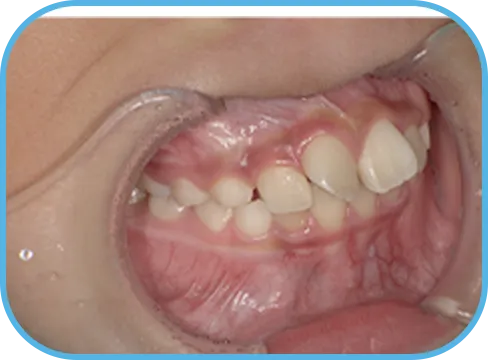

• Before

• 正 面

治療前正面からの歯の様子

• 上 顎

治療前上顎からの歯の様子

• 下 顎

治療前下顎からの歯の様子

• 右 側

治療前右側からの歯の様子

• 左 側

治療前左側からの歯の様子

主 訴

前歯がでている、噛み合わせが深い

治療内容

インビザライン・ファースト

治療期間

10か月

治療費(税別)

450,000円+診断料30,000円

リスク・副作用

• 親知らずの影響や加齢などによって、凸凹が生じる可能性があります。

• 治療の初期段階では痛みや不快感が生じやすくなりますが、1週間前後で慣れます。

• 顎の成長発育によって、噛み合わせや歯並びが変化する可能性があります。

• 状況により当初予定した治療計画を変更する可能性があります。